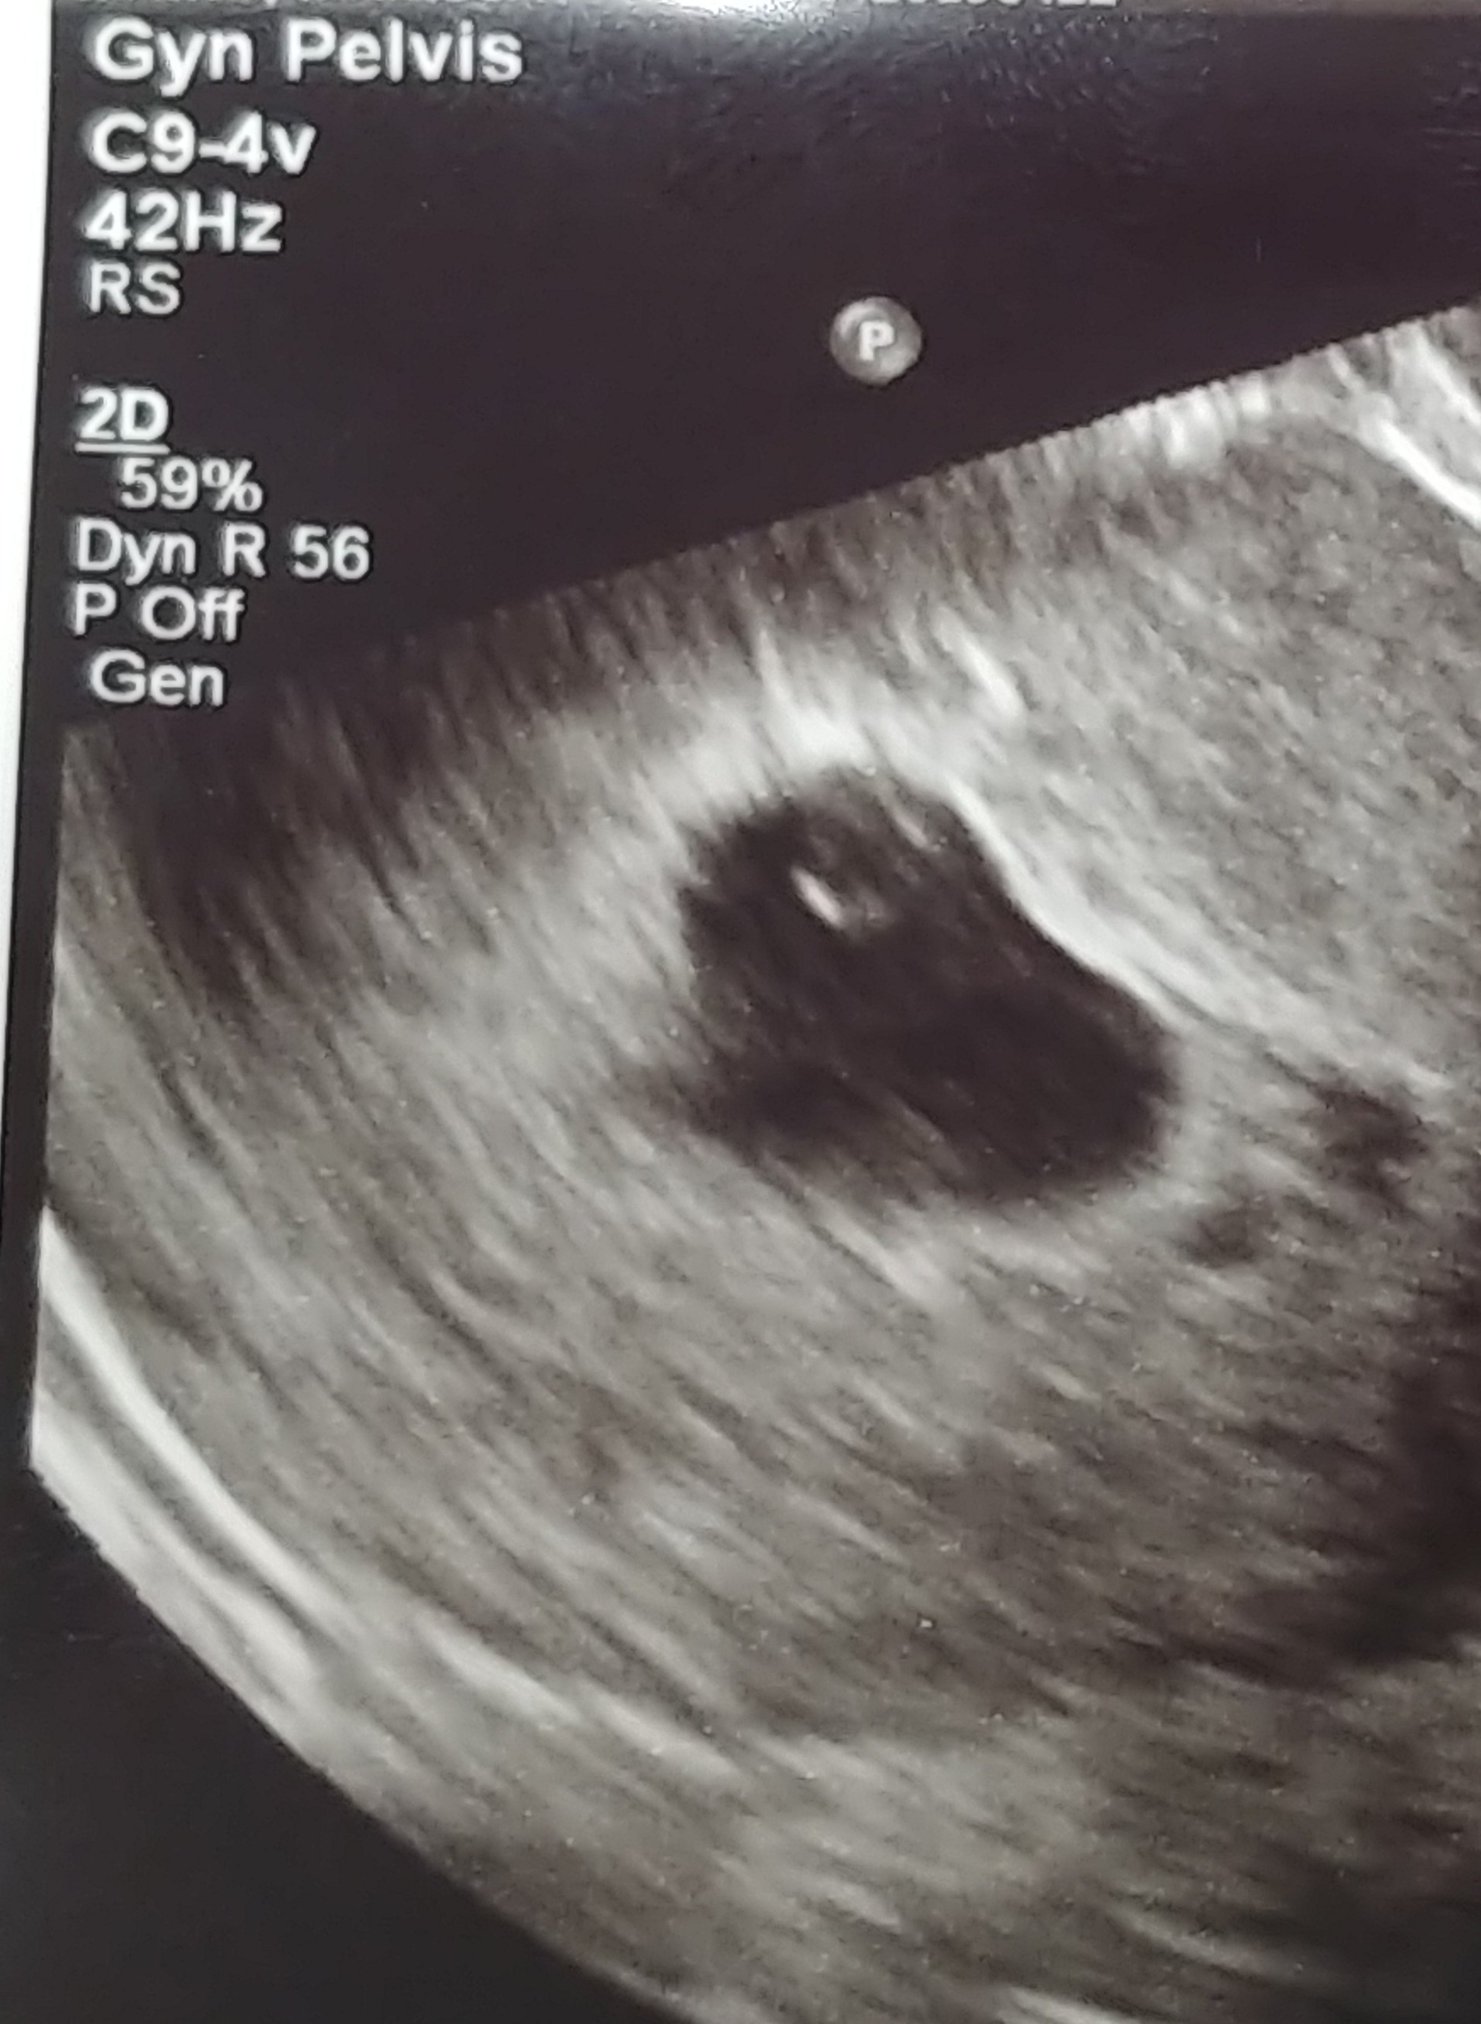

Not too much to see but there's a little baby there with a heartbeat of 122 BPM

The two black dots to the right are the hematoma bleeds😥 Pic was taken far away like this because they are more focused on the SCH.

Since I am very high risk i will be getting weekly ultrasounds to watch the bleed. Praying next week the baby will have grown and the hematoma will be smaller. Keeping faith.